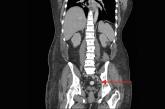

43-year-old male • fatigue • unintentional weight loss • pancytopenia • Dx?

► Fatigue

► Unintentional weight loss

► Pancytopenia